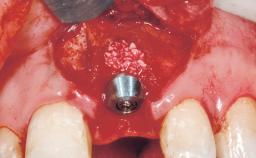

A 29-year-old female patient presented for treatment to replace the upper left central incisor tooth with an implant- supported restoration. The tooth had been intermittently symptomatic for the previous 12 months. The tooth had originally suffered trauma about 15 years previously. Several endodontic treatments had been performed, including an apicectomy procedure to retain the tooth. The patient was healthy and a non-smoker. She had reasonable expectations in regard to esthetic outcomes and the risk of marginal tissue recession following treatment. At medium smile, the gingival margins of the upper teeth were visible, with a display of 3 to 4 mm of the gingival margins. Gingival recession of tooth 21 and a discrepancy in the gingival levels between teeth 11 and 21 was observable during normal speech and smile.

| # of Implants | 1 |

| Type of Implants | One-Piece |

| Attachment | One-Piece |

| Placement Protocol | Immediate implant placement |

| Tooth Site | Maxillary incisor or canine |

| Socket Morphology | Single-root socket |

| Socket Integrity | Damage to one or more bone walls |

| Bone Volume | Damage to one or more socket walls |